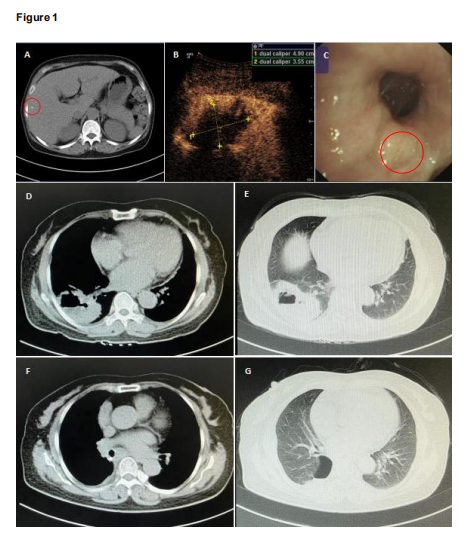

患者感染指標(biāo)普遍升高,腫瘤標(biāo)志物(SCC,CYFRA21_1,CEA)指標(biāo)較高,全腹 CT 顯示肝內(nèi)膽管小結(jié)石,肝囊腫,余未見明顯異常。胸部 CT 現(xiàn)實(shí)右肺下葉高密度腫塊,病灶內(nèi)多發(fā)空洞,可見氣液平面,空洞周圍邊界模糊,可見不規(guī)則磨玻璃樣陰影。右肺下葉包裹積液、積氣,考慮膿腫。培養(yǎng)見念珠菌屬+(痰)和曲霉菌 1cfu(肺泡灌洗液)。初步診斷為肺膿腫。

影像學(xué)檢測結(jié)果:

胸部 CT,彩超,氣管鏡。右肺下葉混合回聲團(tuán)塊-考慮病灶內(nèi)部含氣體液化壞死區(qū)。主氣管通暢,未見分泌物,左、右主支氣管及各葉段支氣管腔內(nèi)未見新生物、異物、出血,右下葉背段支氣管腔內(nèi)可見少量白粘痰。